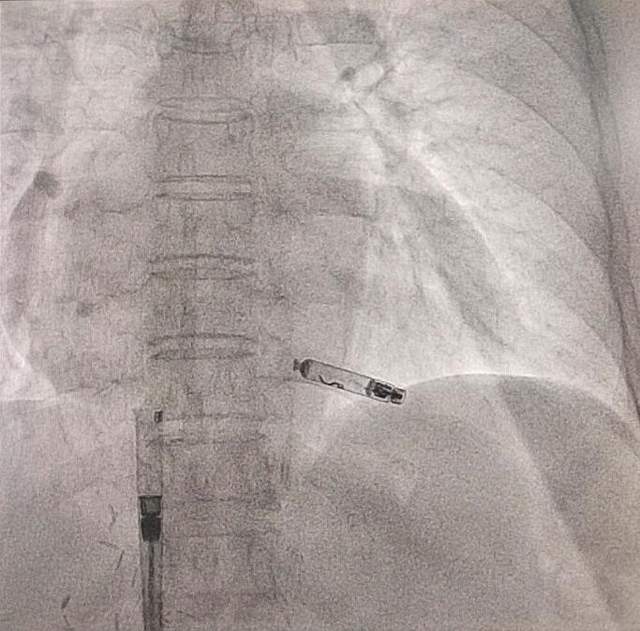

5月21日,手术如期进行,心血管科团队仅通过右侧股静脉穿刺,便将胶囊大小的无导线起搏器精准植入患者右心室间隔部。术中实时监测参数,确保了起搏效能。得益于微创技术,患者术后即刻恢复稳定心率(50次/分),并在术后6小时实现了床上自主活动。

无导线起搏器被精准植入患者右心室间隔部